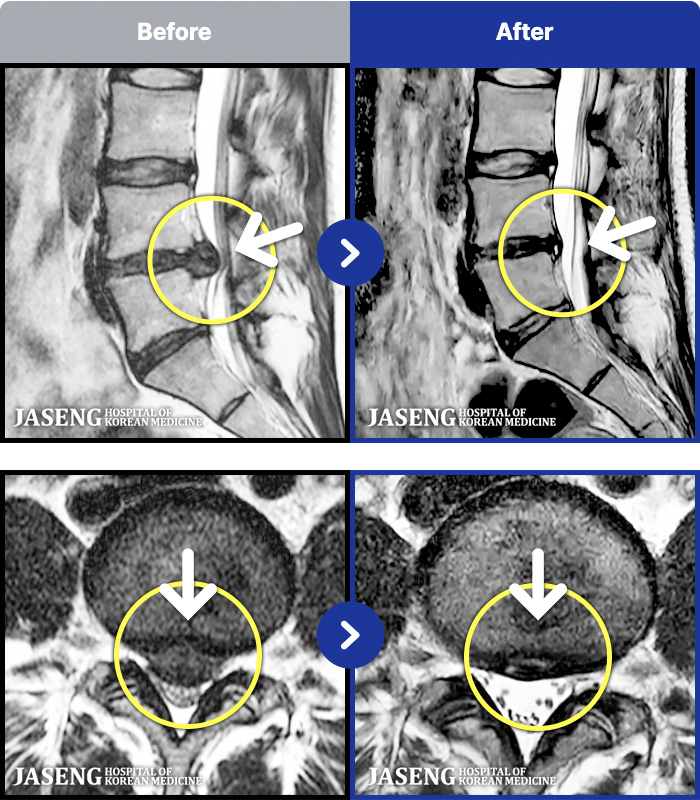

1,286 MRI ũ ʸ Ȯϼ.

ȯںп Ǹ ǿ ԿǾ, ο ġ ۿ Ƿ ġḦ Ͻñ ٶϴ.